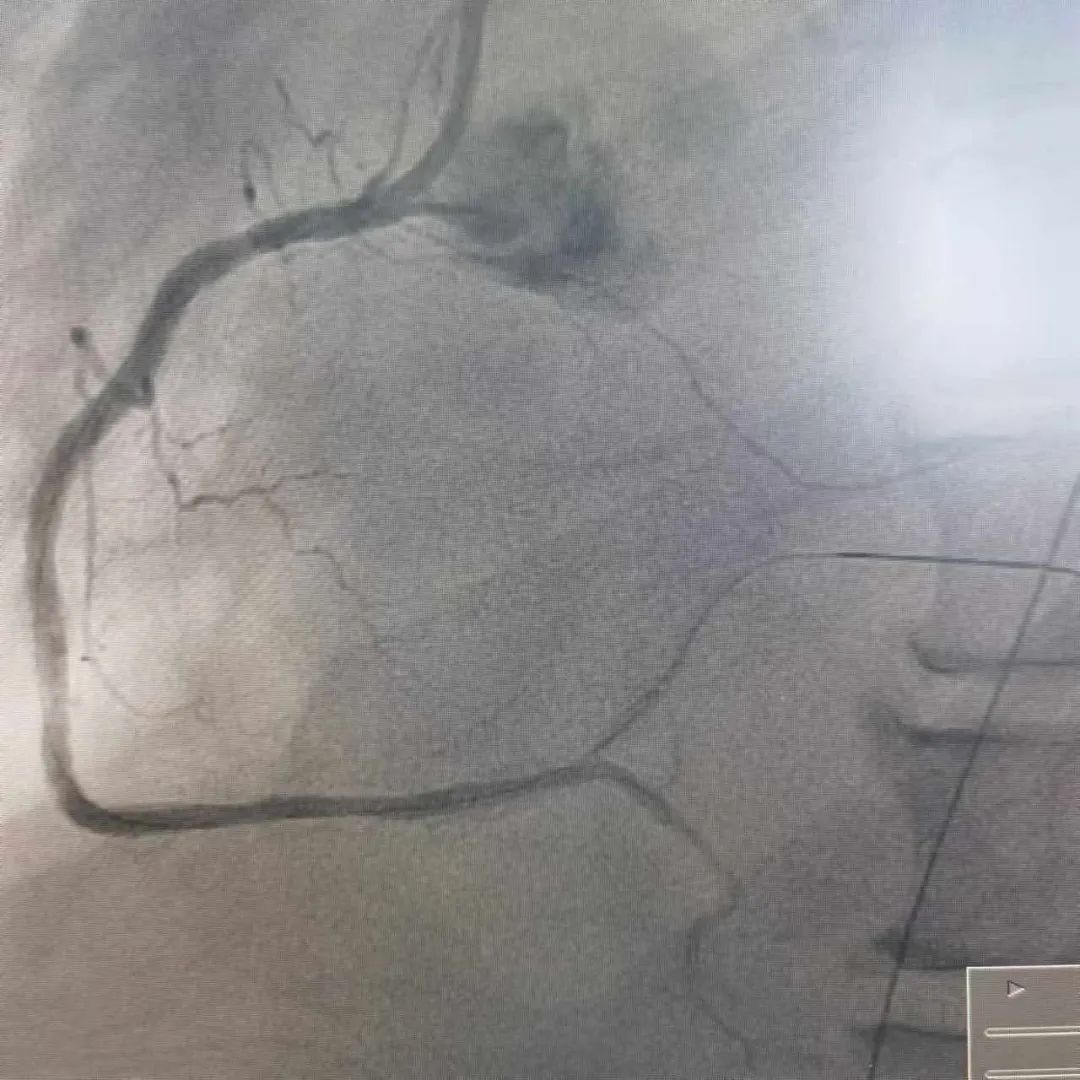

近日,玉山县黄家驷医院(玉山县人民医院)医护团队和玉山县博爱医院医护人员共同上演了一场“生命接力赛”,经过近7小时的救治,成功抢救一名呼吸心脏骤停、急性心肌梗死的重症患者。

10月17日,家住玉山县的何先生因胸闷气憋入住玉山县博爱医院,然而,在就诊过程中突发呼吸心跳骤停……医护人员立即予以心肺复苏、气管插管、电除颤等急救措施直至患者恢复自主心率,但意识仍丧失。考虑到患者病情危重,博爱医院医护团队与患者家属沟通后,即刻转至玉山县黄家驷医院(玉山县人民医院)继续救治。

发生急性心肌梗死,要采取就近抢救原则,及早送至有经皮冠状动脉介入治疗(PCI)能力的医院行PCI治疗,如就诊医院无法行PCI治疗,建议立即转至附近有PCI能力医院行PCI治疗或溶栓治疗,尽量缩短发病时间至开通闭塞血管的总缺血时间,总缺血时间越短,患者的生存率及康复率就越高。

我院胸痛中心为胸痛患者24小时开通生命“绿色通道”,早发现早诊断早治疗,能争分夺秒为患者开通闭塞血管,挽救濒死的心肌,缩小梗死的面积,保护心脏功能,及时处理心肌梗死的各种并发症,是玉山及周边地区心梗患者救治的较佳选择。

自 2021 年 4 月我院启动胸痛中心建设以来,全院上下高度重视、全员动员,有序地推进各项工作的开展,胸痛中心建设工作不断完善,于2023年8月通过国家级胸痛中心认证,成为国家级胸痛中心的一员。这标志着我院对急性心肌梗死等高危胸痛的救治水平、流程优化、硬件设施等方面均已达到国家级标准。

在推进胸痛中心建设中,我院严格做好有指征的筛查工作,就诊的病人在增加,冠脉介入术数量在增加,介入自主完成率也越来越高(急性心梗介入手术自主完成率达100%),心梗患者在本地发现率、救治率均明显提升,获得了明显的社会效益。在全市的排名中:2024上半年,急性心梗收治100例,冠脉介入手术120例,两项均位列全市第二名,仅次于上饶市人民医院,已领先于同级县医院。